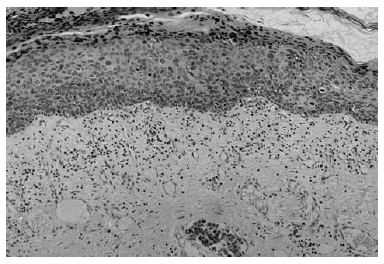

Se realizó una biopsia amplia de la lesión, incluyendo la tumoración nodular. En el examen histopatológico se podía observar una epidermis eosinófila, con una desestructuración que afectaba todo su espesor, ocupada en todo su grosor por queratinocitos atípi-cos con frecuentes mitosis, la mayoría de ellas atípicas. En el estrato córneo había hiperqueratosis, con áreas de paraqueratosis. En dermis superficial existía un infiltrado inflamatorio crónico en banda formado predominantemente por linfocitos con algún histiocito aislado (fig. 2).

Fig. 2.--Alteración de todo el espesor de la epidermis circundante, con paraqueratosis, células disqueratósicas y mitosis.

El diagnóstico clínico requiere siempre la confirmación histológica, en la cual se observan cambios que afectan a todo el espesor de la epidermis, con queratinocitos atípicos. Esto se asocia con desórdenes en la maduración de la epidermis, mitosis en diferentes niveles, queratinocitos multinucleados y células disqueratósicas. Frecuentemente existe pérdida de la capa granulosa, con paraqueratosis y excepcionalmente hiperqueratosis. El epitelio atípico puede también afectar la unidad pilosebácea, lo cual explica el frecuente fracaso terapéutico cuando se utilizan métodos de destrucción superficiales para el tratamiento5.